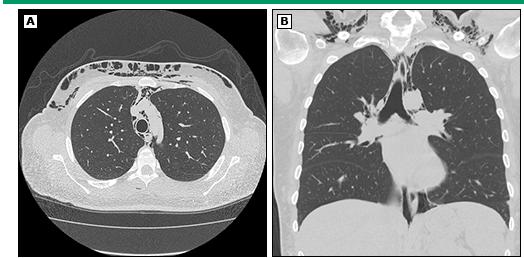

自发性纵隔积气是炎性肌病一种罕见但严重的并发症。皮肌炎更常见该并发症,尤其是「无肌病性皮肌炎」。有研究显示,约50%的自发性纵膈积气发生在「无肌病性皮肌炎」病人身上。纵隔积气的典型表现是急性发作的胸骨后胸痛伴皮下气肿。这时可以视察到颈部和面部肿胀。医生按压皮肤时有明显的「握雪感」,甚至可以听到沙沙的气体被挤压声音。

自发性纵膈积气